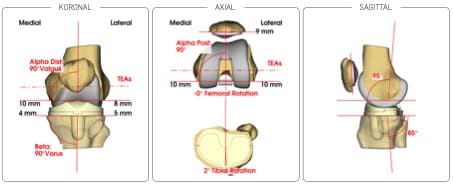

Ich verwende ein komplett neues System von der Firma Symbios. Dieser Kniegelenksersatz ist eine komplette Maßanfertigung. Es bedeutet, dass diese Knieprothese speziell nur für Ihr Knie angefertigt wird.

Ihr Knie wird zuvor genauestens ausgemessen und unmittelbar danach produziert. Es steht nach 6-7 Wochen für die Operation zur Verfügung.

- minimale und sparende Knochenresektion

- mehr Präzision durch 3D Planung

- an Ihr natürliches Knie angepasste Geometrie